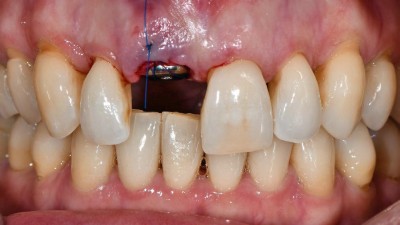

Sofortimplantation bei einer parodontal kompromittierten Patientin nach abgeschlossener kieferorthopädischer Behandlung im Erwachsenenalter

Die implantologische Versorgung parodontal kompromittierter Patienten erfordert ein hohes Maß an interdisziplinärer Planung und klinischer Präzision. Im vorliegenden Fallbericht wird die Versorgung einer Patientin mit fortgeschrittener Parodontalerkrankung beschrieben, bei der im Anschluss an eine abgeschlossene kieferorthopädische Therapie ein nicht erhaltungswürdiger Frontzahn extrahiert und unmittelbar durch ein Implantat ersetzt wurde. Dabei stellten sich mehrere Herausforderungen...